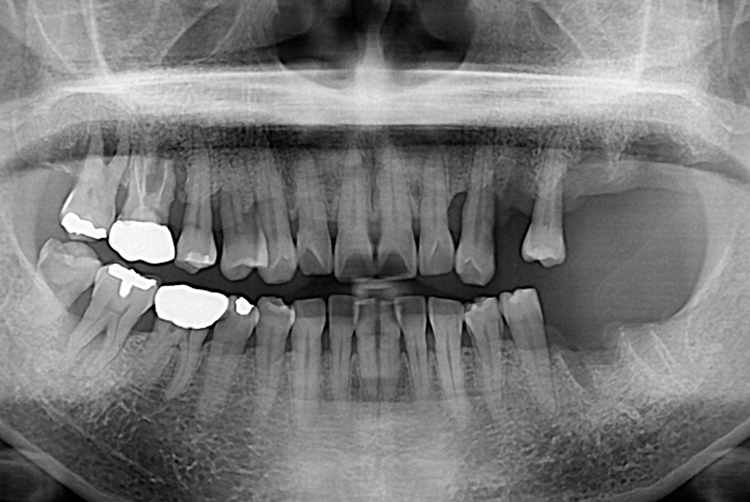

[임플란트] 임플란트

1221 권은숙_후.jpg

치료후 : 2019-10-24

세종치과는 많은 환자와 다양한 케이스를 바탕으로 항상 편안한 임플란트 수술을 제공하고자 노력하고,

오래동안 튼튼히 쓸 수 있는 임플란트 수술을 가장 큰 목표로 삼고 있습니다